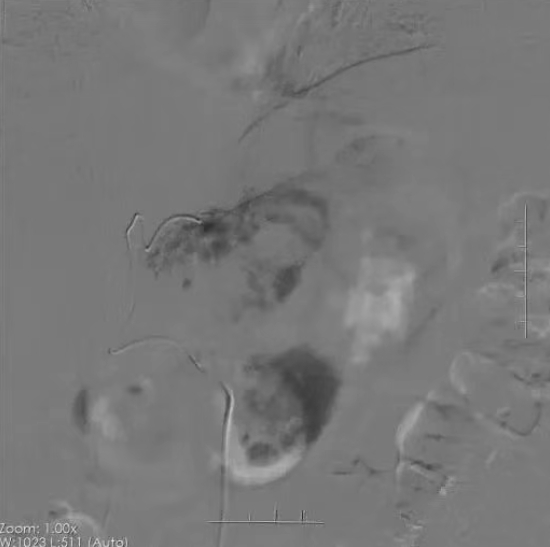

病例分享二

术前增强CT示肝右叶肿块伴门脉瘤栓形成

术中造影、栓塞、注射化疗药物